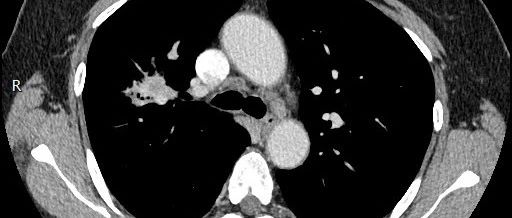

这种「胸水」,做胸腔穿刺要出大事!

*仅供医学专业人士阅读参考一不小心,就成了骚操作!胸腔积液,胸腔穿刺,都是呼吸内科很常见的临床问题,一般很简单,但是,越是简单,越要小心谨慎,小心驶得万年船。一不小心,就成了骚操作!下面这个CT,感觉如何?外院做的CT,片子不是很清楚。实习同学一看,兴奋地跳起来:"老师,大量胸腔积液,胸腔穿刺,走起!并且报告也说胸腔积液。”一个进修医生也说:“可以留置引流管了。”之前查阅国外文献,看到别人入坑、吃亏、被套路。...